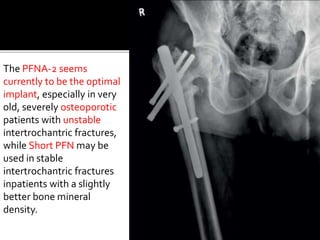

The PFNA-2 seems

currently to be the optimal

implant, especially in very

old, severely osteoporotic

patients with unstable

intertrochantric fractures,

while Short PFN may be

used in stable

intertrochantric fractures

inpatients with a slightly

better bone mineral

density.